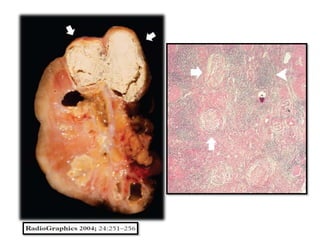

Con el tiempo, los granulomas inflamatorios

confluyen, caseifican y se extienden hasta la médula

renal, con la resultante inflamación y necrosis de la

papila renal.

Las lesiones del parénquima se comunican con el sistema

colector por medio de la formación de ulceraciones

caliciales.

La extensa calcificación que causa cálculos renales o

considerables cambios parenquimatosos pueden verse

en hasta el 24% de los pacientes.

Riñones

La afectación bilateral se encuentra hasta en el 20- 30 % de los

casos.

En la radiografía simple, un tamaño renal variable puede

apreciarse.

Las Calcificaciones, que ocurren en más de 50% de los

pacientes, puede adoptar varias formas. Pueden ser

focales, que se producen en los restos de caseum, o como

cálculos en el sistema colector.

En los casos de tuberculosis en fase terminal, las

calcificaciones características que muestra una distribución

lobar son menudo encontradas.

En última instancia, un riñón totalmente calcificado y no util

puede verse, que representa etapa final de

enfermedad, denominada autonefrectomia.